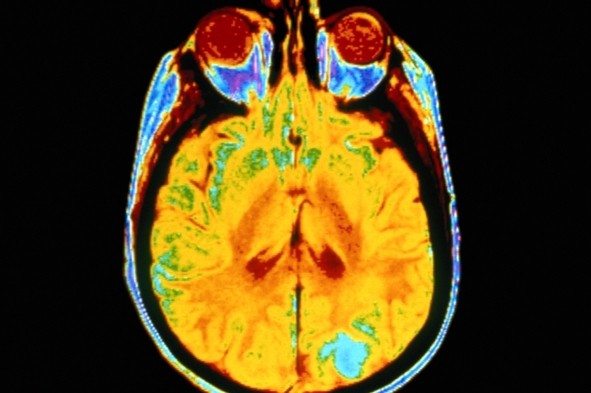

در روش UCLA محققین از یک ابزار آزمایشی استفاده نمودند که حدودا به اندازه یک فنجان نعلبکی، برای تمرکز امواج اولتراسونیک بر روی تالاموس بود. ساختار تالاموس به شکل دو توده در اندازه گردو در مرکز مغز است که به عنوان کانون حیاتی برای جریان اطلاعات و کمک به تنظیم هوشیاری و خواب عمل می کند.

این مغز فعال شده متعلق به بردلی کرهان بود.